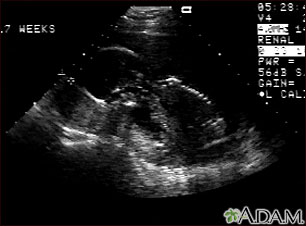

Ultrasound, normal fetus - profile view

Ultrasound, normal fetus - profile view

This is a normal fetal ultrasound performed at 17 weeks gestation. In the middle of the screen, the profile of the fetus is visible. The outline of the head can be seen in the left middle of the screen with the face down and the body in the fetal position extending to the lower right of the head. The outline of the spine can be seen on the right middle side of the screen.